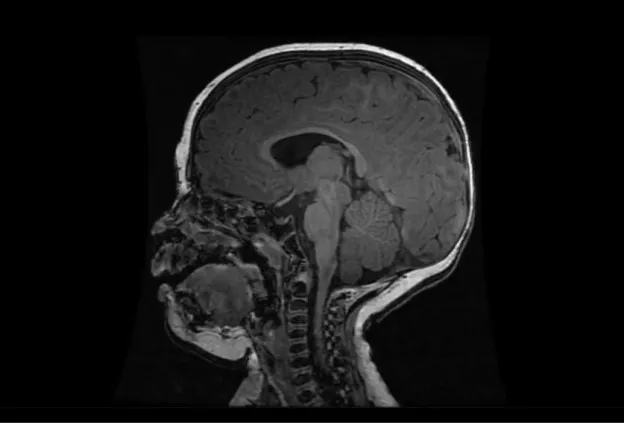

The Birth Asphyxia MRI (BAMRI) study implements innovative imaging techniques to assess infants who have encephalopathy in the neonatal period.  The study also evaluates the children as they mature to determine the long term effects of neonatal encephalopathy on brain development and neurodevelopmental performance.